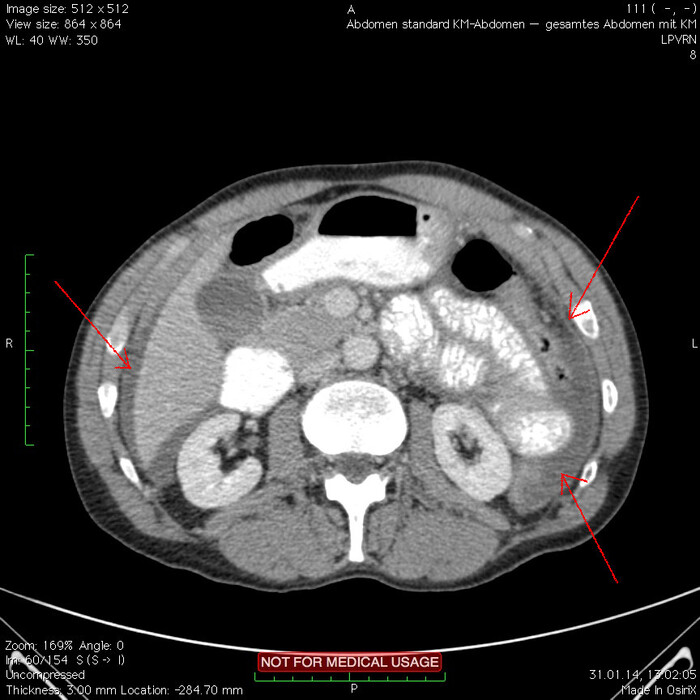

Мужчина, 32 года. Во время игры в футбол получил удар в низ живота, игру продолжил. Впоследствии боли в животе усиливались, стали нестерпимыми, ухудшилось общее самочувствие. На следующий день после игры пошёл сдаваться в больницу. Хирурги клинически описывают разлитой перитонит (воспаление брюшины) и отсылают пациента к нам на КТ, которое мы провели с внутривенной дачей контраста + заставили контраст ещё выпить (специальный раствор для перорального применения).

Так как клиника у нас острого живота после тупой травмы, учитывая что боли во всём животе и признаков большой кровопотери нет, то первое, что ищем - это свободный газ в брюшной полости, и находим его! (для этого лучше всего подходит т.н. лёгочное окно, как представлено ниже, или можно искать в костном окне - это спец.настройки яркости и контраста для просмотра разных структур тела - лёгкие, мозг, мягкие ткани, кости):

Отмечаем про себя, что в верхних квадрантах свободного газа не так уж и много. При перфорации желудка газа намного больше. Также выясняем, что газ есть также и в нижних квадрантах:

Ещё бросается в глаза массивный выпот (стрелки) во всех этажах, а также утолщение брюшины на всём протяжении, что указывает на диффузный (разлитой) перитонит. Тут, кстати, уже мягкотканное окно:

Итак, имеет место быть свободный газ в брюшной полости + свободная жидкость + перитонит. Определённо перфорация! Осталось найти источник. Желудок не подходит по механизму, а точнее по локализации травмы. Мочевой пузырь - в нём нет воздуха. Остаётся методом исключения только кишечник. Толстый или тонкий? Явно не верхние отделы толстого кишечника (ободочная кишка в области печеночного и селезеночного углов, а также поперечная исключаются - было бы больше воздуха). Сигма и нисходящая тоже заполнены стулом и воздухом. Получается, что тонкий кишечник всему виной.

Верхние (проксимальные) отделы точно не причём. Жидкость (звёздочки) больше в малом тазу, тут же и воздух. Для сравнения верхний этаж:

Hижний этаж:

И тут СТОП! А это чтo такое???

Кишке это точно не принадлежит, как ни крути. Это вышедший за пределы кишки контраст, который пациент выпил!

Осталось только место выхода найти:

Итого: перфорация тощей кишки в дистальных отделах, разлитой перитонит.

Был успешно прооперирован, место перфорации ушито, выписан.